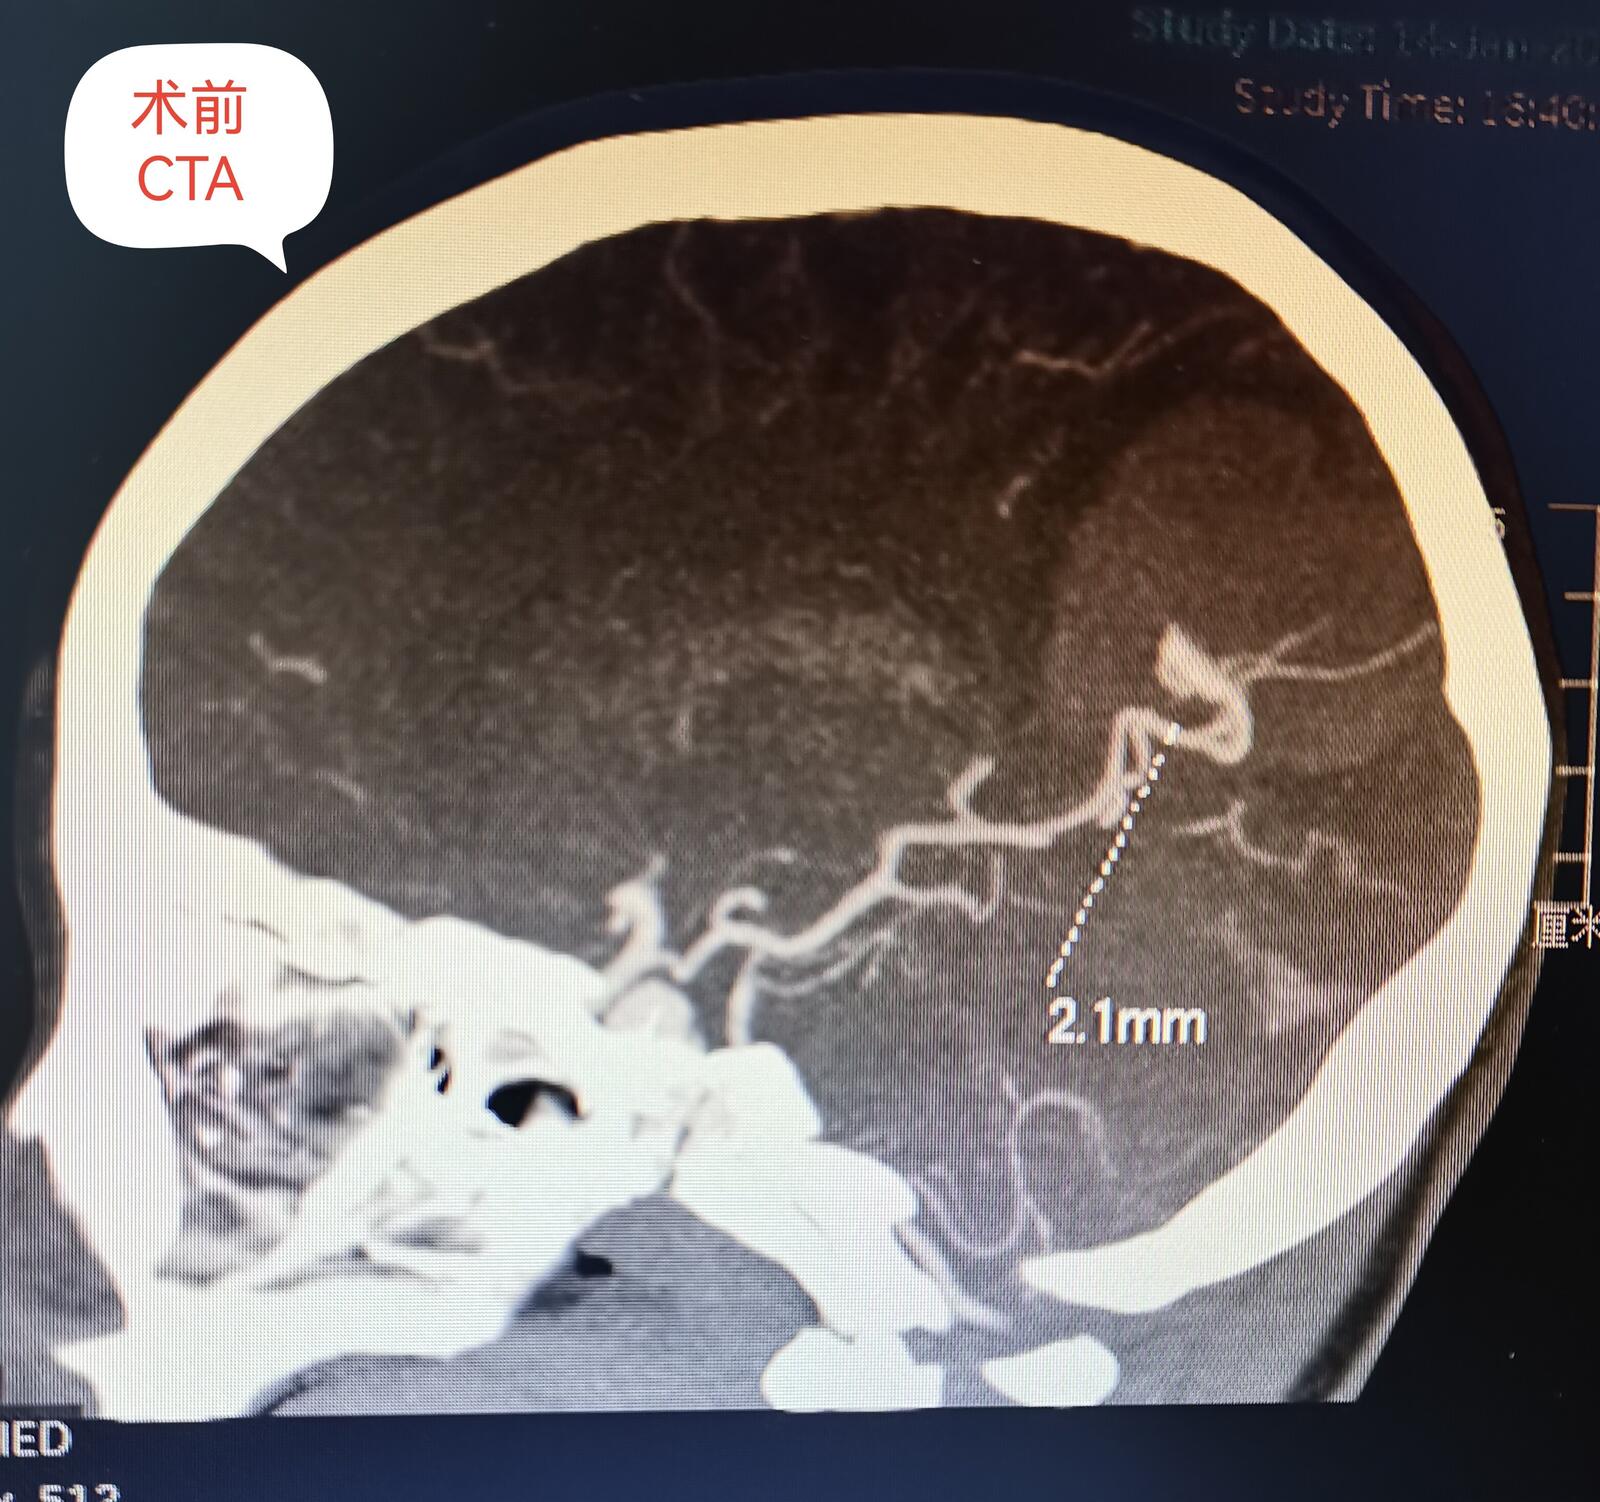

脑血管畸形主要以儿童期和青少年发病为主,儿童主要以头疼、癫痫和出血发病就诊。检查脑CTA、MRA,金标准为全脑血管造影(DSA)。治疗包括DSA介入栓塞(就是我们老百姓常说的微创手术)和开颅畸形团切除术以及伽马刀治疗,各有利弊额,也要更具患儿具体情况个性化定制治疗方案。今日展示一例8岁男童右侧枕叶脑血管畸形(AVM)破裂出血血肿急诊开颅血肿清除+荧光显微镜下畸形团全切手术。患儿入院单侧瞳孔散大,脑疝形成,已不适合介入治疗,甚至复合手术会耽搁救治。现患儿经治疗痊愈出院,无神经功能后遗症表现。后期在造影复查,修补颅骨。